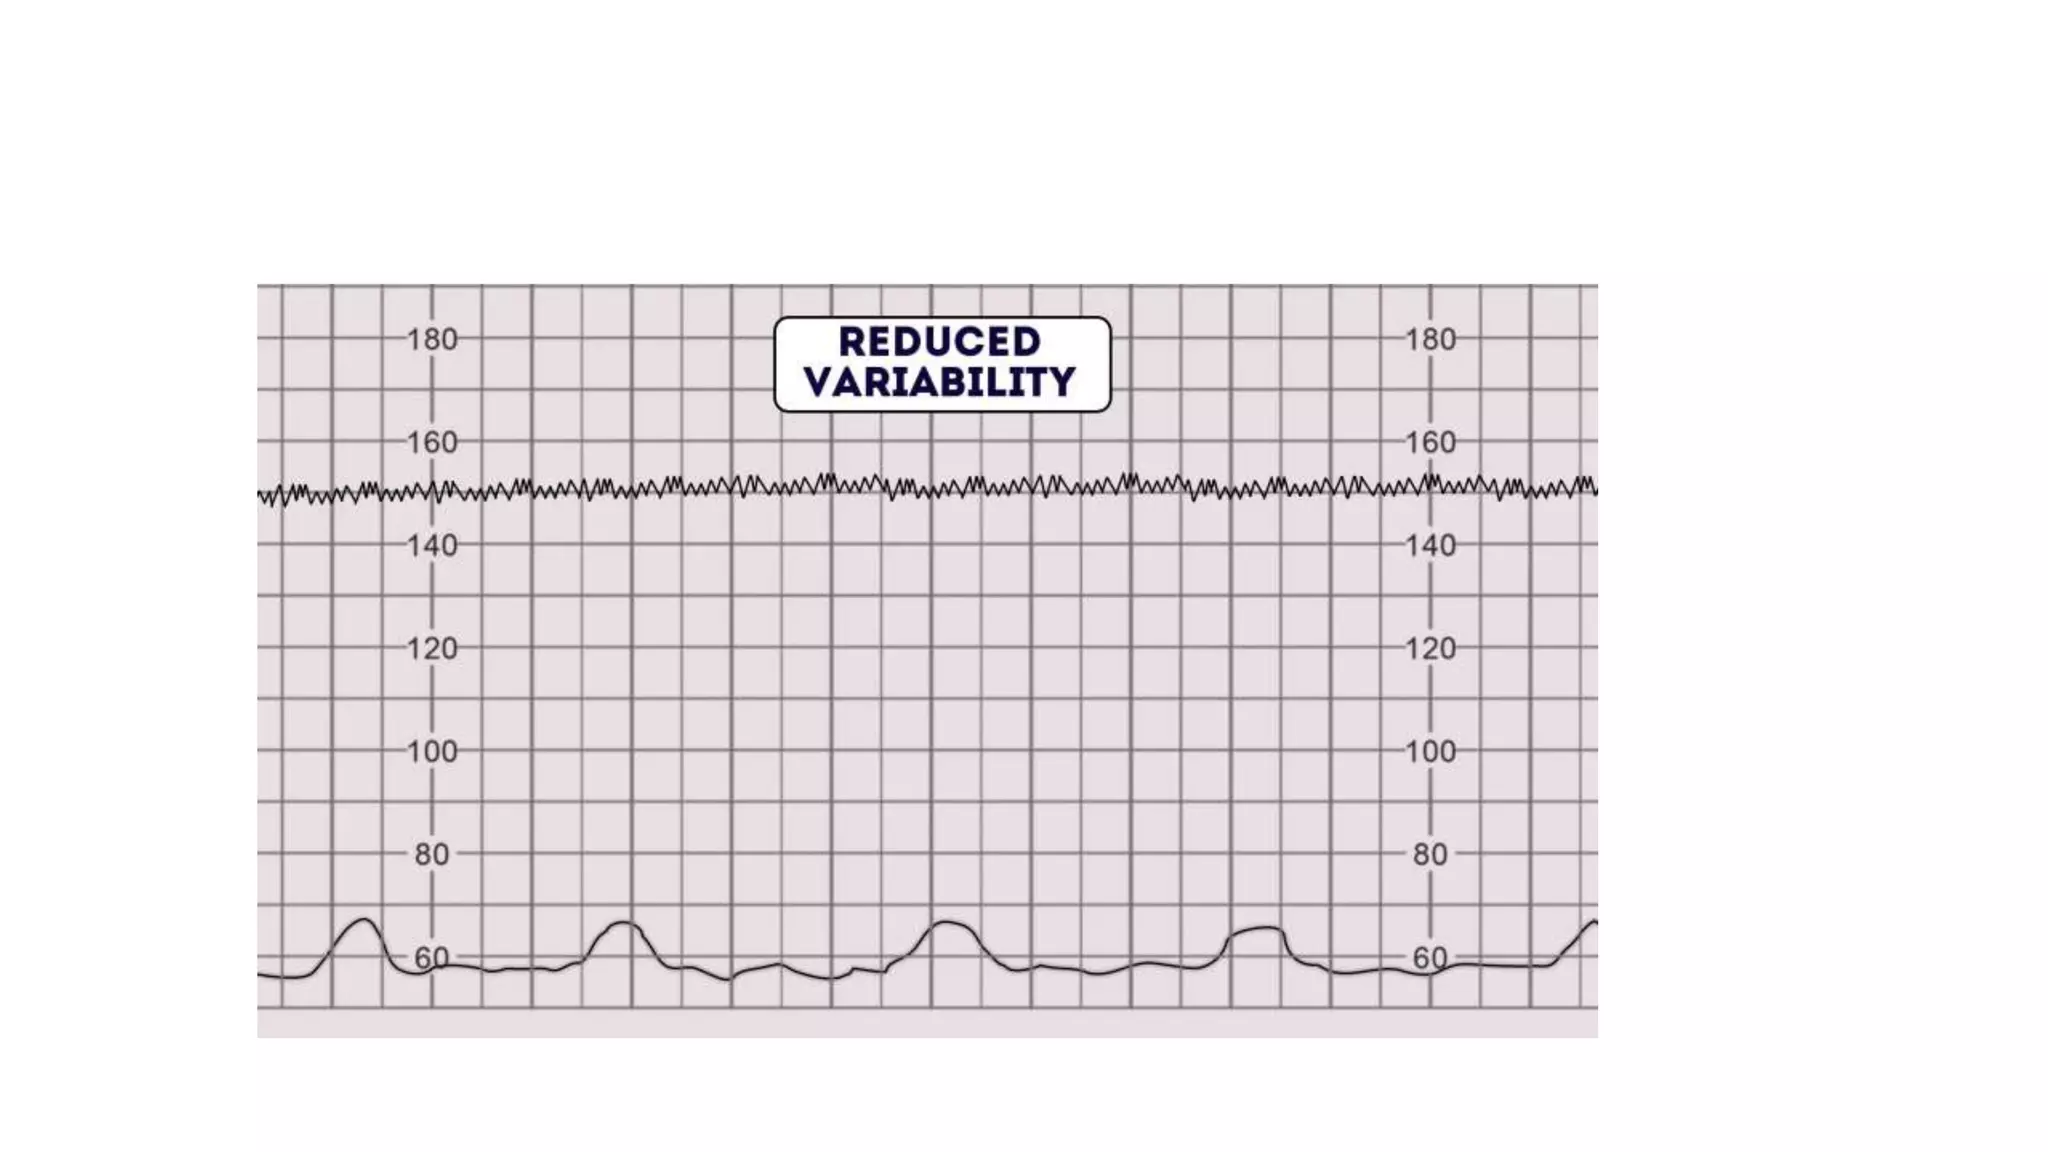

The document discusses key metrics for monitoring a baby's heart rate in utero, including the normal baseline rate of 100-160 bpm and variability. It also covers types of accelerations and decelerations that can occur, such as early or late, as well as bradycardia, which is an abnormally slow heart rate.